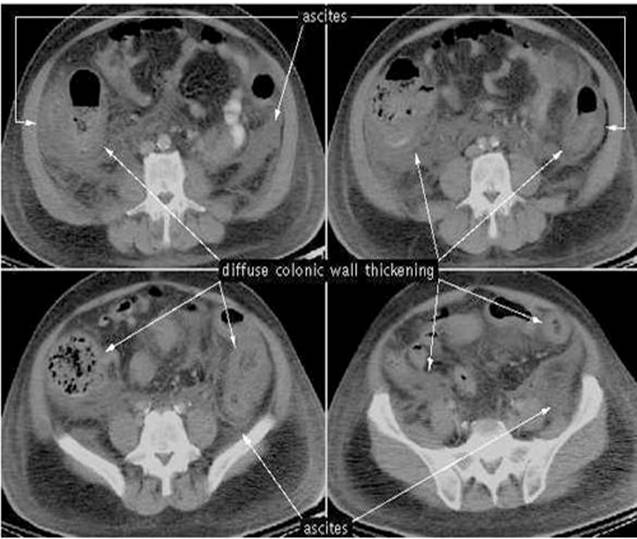

Hình ảnh viêm đại tràng màng giả trên phim chụp CT scan.